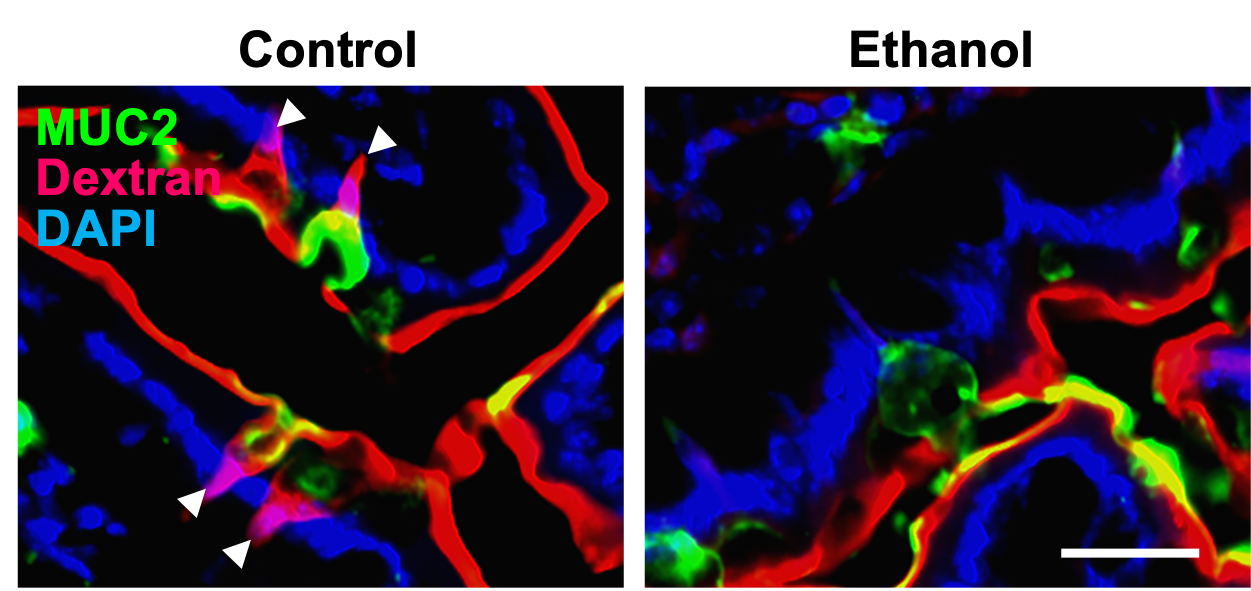

Alcohol Disrupts mAChR4-GAP-Mediated Barrier Function. Chronic alcohol exposure in both humans and mice downregulates mAChR4 expression and related pathway transcripts, leading to reduced GAP formation. mAChR4 downregulation strongly correlates with ALD progression in patients with AUD. Our preclinical models demonstrate that GAP closure is mediated through MAPK. This impairs barrier function by disrupting antigen sampling by LP-APCs, weakening antimicrobial immunity (REG3), and facilitating pathogenic bacterial translocation, a key driver of ALD progression.

Alcohol reduces mAChR4 and GAP formation. Figure from Llorente et al., Nature, 2025